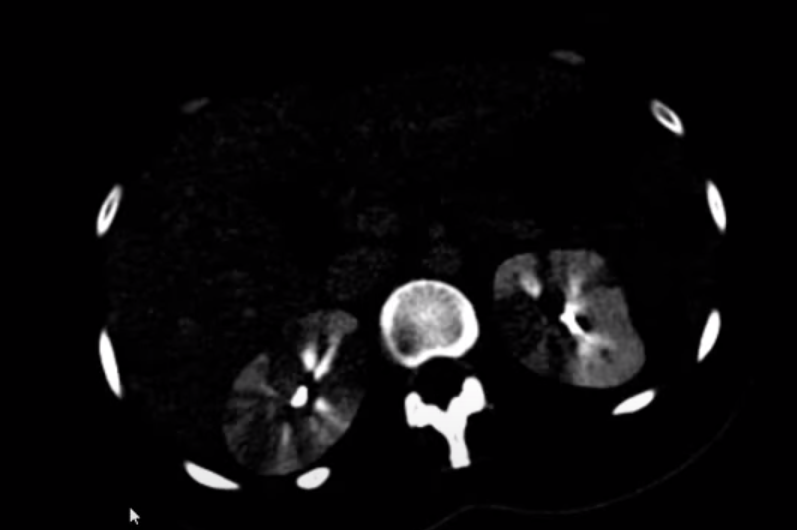

Homem, 74 anos, fibrilação atrial.

Dor abdominal aguda.

Infarto tromboembólico da artéria renal direita.

Região hipodensa com defeito de realce em forma de cunha.

Sinal do realce cortical ocorre geralmente após 24 horas do infarto e consiste no realce da margem periférica do rim na fase nefrográfica, no contexto isquemico. Ocorre em cerca de 50% dos casos.